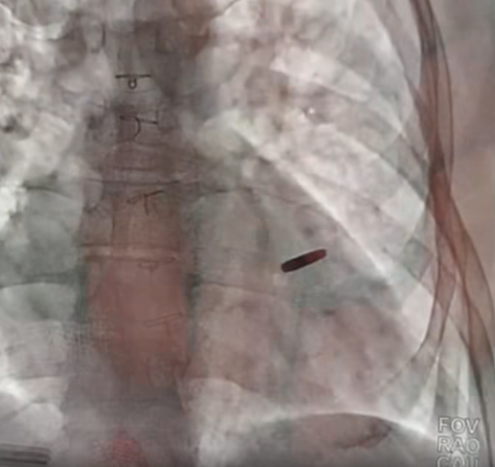

Відповідне відео опублікував на своїй Facebook-сторінці лікар-кардіохірург Борис Тодуров. Він наголосив, що бійцю дуже пощастило.

"(Куля. – Ред.) знаходилася в серці нашого хлопця, який три роки провів у полоні, захищав разом з азовцями "Азовсталь". Пораненого взяли в полон під час атаки на Маріуполь", – розповів медик.

Він додав, що захисник повернувся додому два місяці тому, під час чергового обміну, і це неймовірне везіння, що куля не пошкодила життєво важливих органів.

"На щастя, вона нічого не пошкодила і зараз ми її видалили. Пощастило хлопцю. Думаю, що він проживе довге і щасливе життя", – сказав Тодуров.